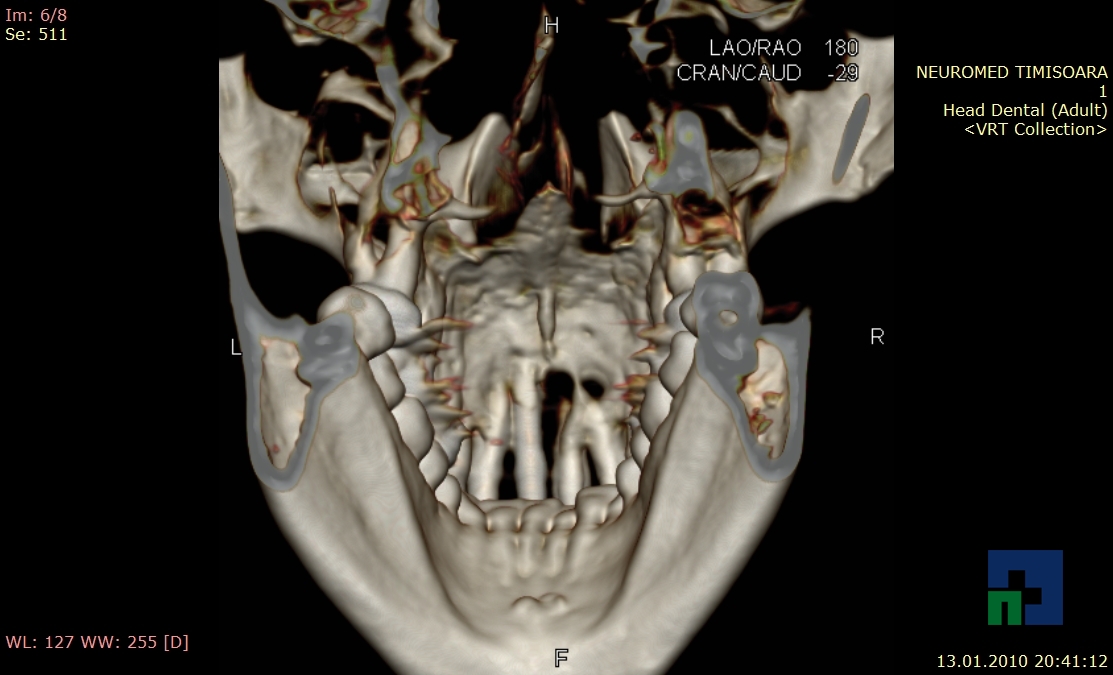

- Diagnosticul fracturilor:

- Complexe cranio-sinusale

- Complexe cranio-etmoidale

- Complexe cranio-orbitare

- Complexe cranio-faciale